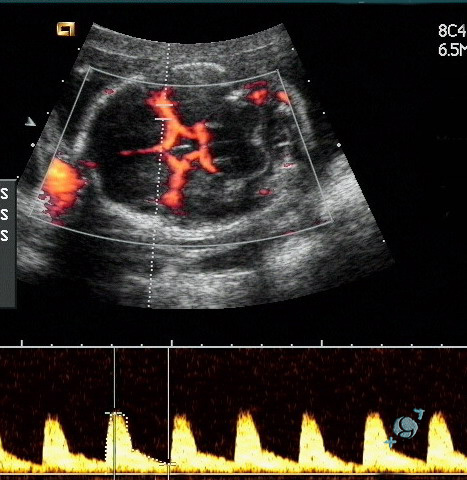

En nuestro centro contamos con un ecógrafo con tecnología de avanzada que puede crear una imagen en color (Doppler a color). El Doppler a color permite visualizar el desplazamiento de los glóbulos rojos por las venas (azul) y arterias (rojo)

En nuestro centro contamos con un ecografo con tecnología de avanzada que puede crear una imagen en color (Doppler a color). El Doppler a color permite visualizar el desplazamiento de los glóbulos rojos por las venas (azul) y arterias (rojo) y mostrar en la pantalla la dirección y la velocidad de la circulación en las cavidades del corazón y en los vasos.

Es una técnica diagnóstica no invasiva que detecta el movimiento y la turbulencia de la sangre. El doppler actúa en forma similar al radar de sonido siendo en este caso los eritrocitos (glóbulos rojos) los que actúan como móviles. Es un método rápido y que puede practicarse cuantas veces se precise sin comportar ningún riesgo para el paciente.